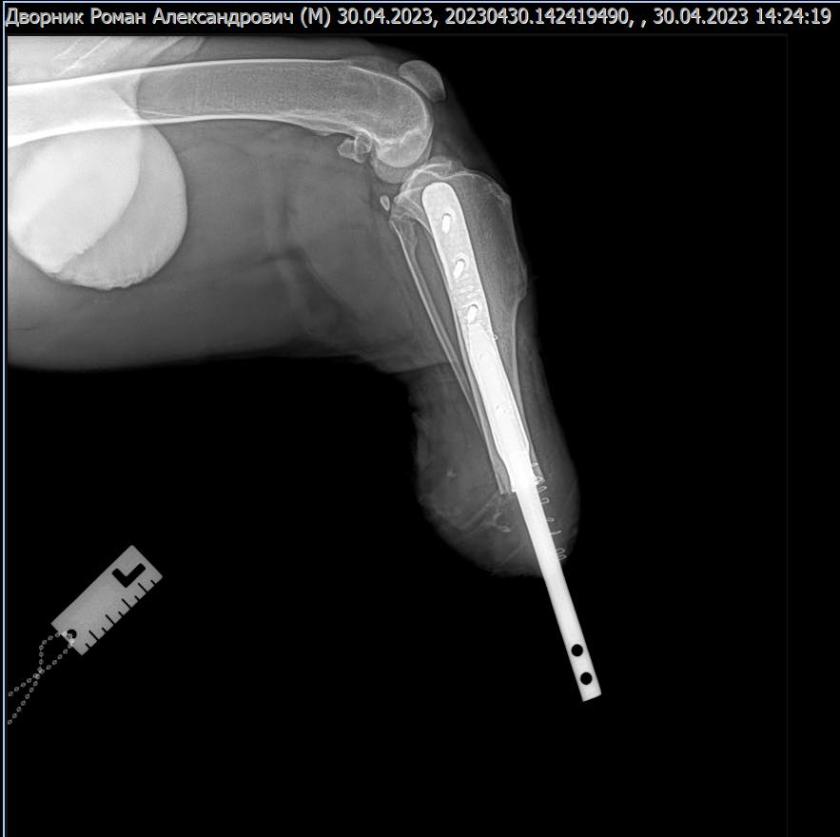

Пораненій тварині, яка перенесла травматичну ампутацію, вживили біоінтегрований протез.

"Сподіваємось на скоре одужання нашого паціента. Подяка власникам, що не кинули свого улюбленця в такі тяжкі часи. Розробка імпланту 3D metal tech!", — написав головний лікар Харківського ветеринарного госпиталю Віталій Клубань у фейсбуці.